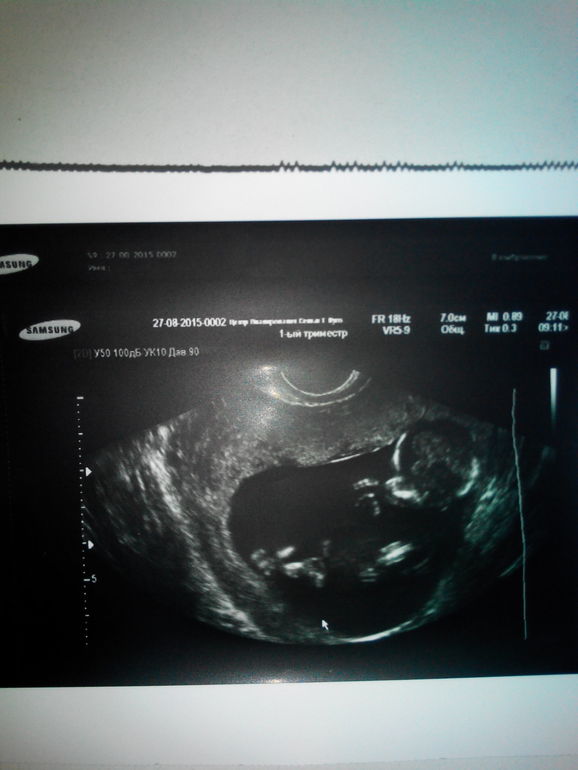

Первый скрининг пройден)

предположительно сказали,что будет мальчик)

все показатели в норме, малышик круть верть,все время двигался)

так мне нравятся фото первого скрининга)))на мой взгляд они самые лучше, хотя многие считают наоборот))) просто на втором скрининге малыш уже полностью в кадр не помещается, и уже выглядит не так эффектно)))